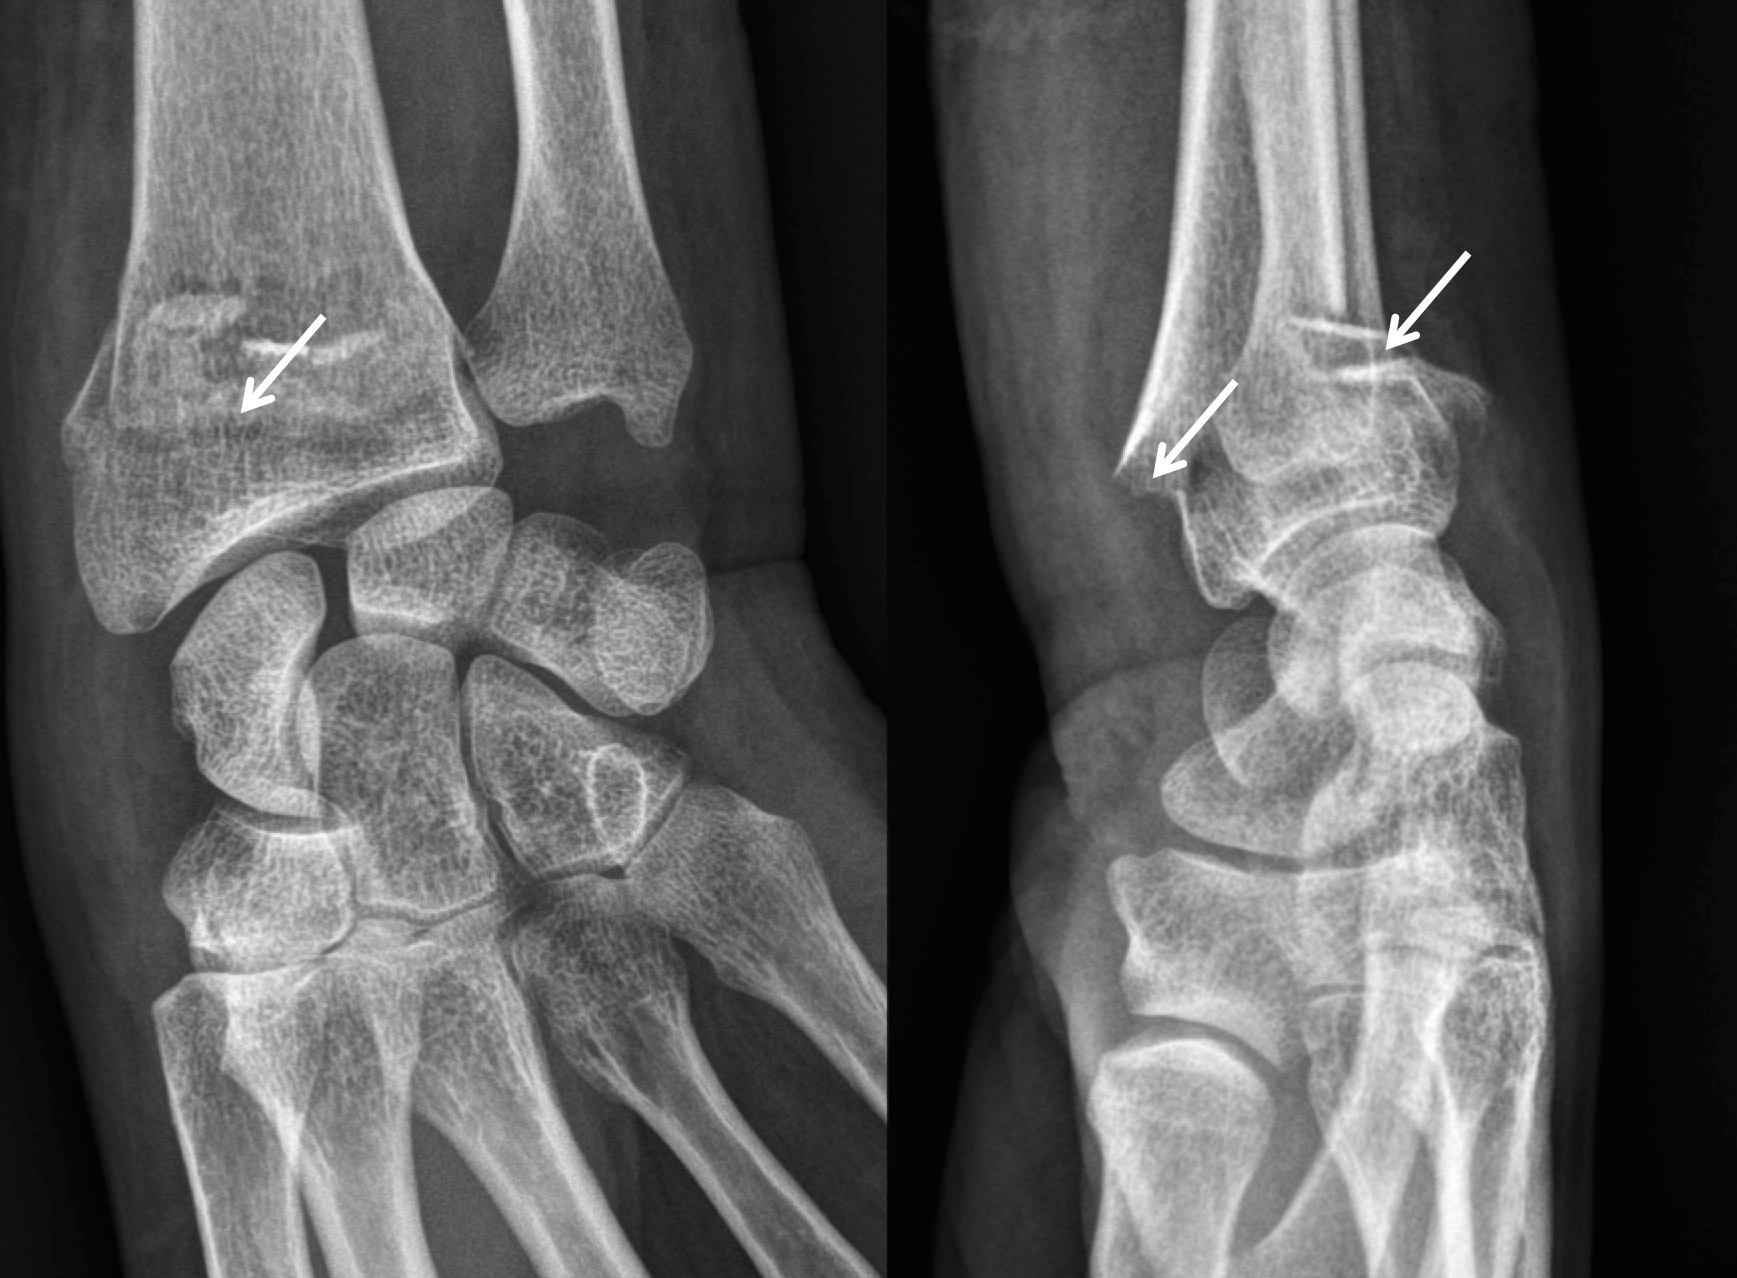

From www.alamyimages.fr

xray montrant une fracture de l'ulna et le radius Photo Stock Fracture Poignet Symptome  Douleur autour du poignet , la main et l'avant. Et quels traitements envisager ?. Toutes les définitions santé, symptômes et traitements sont sur docteurclic. Une douleur intense au niveau du poignet, qui peut irradier vers la main ou. Chute, accident de sport ou de travail. Les symptômes d’une fracture du poignet sont variables. Les symptômes d’une fracture du poignet sont. Fracture Poignet Symptome.